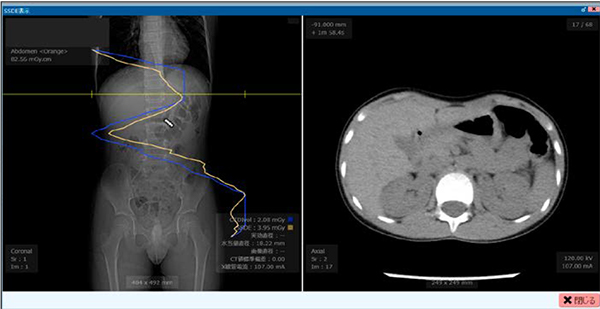

SSDE解析表示例

AAPM Task Group 220によるSSDEをスライス位置ごとに算出し,位置決め画像上にグラフ表示。位置決め画像上でカーソルを移動させることで,任意のスライス位置でのSSDE値を表示可能である。この表示例では,SSDE(黄色)と同時にCTDIvol(青色)も表示している。

その他選択することで管電流値,水等価直径値なども表示可能である。